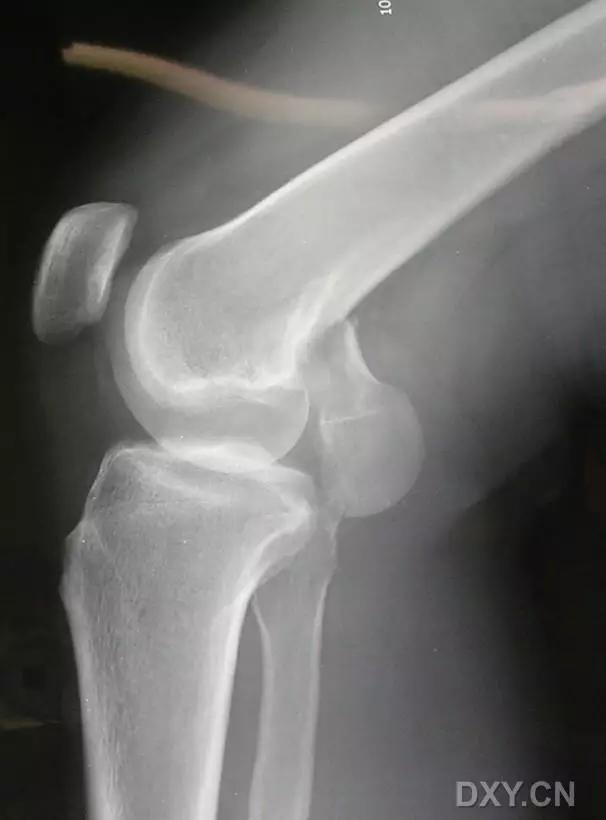

(2)反向 Segond 骨折

胫骨平台内侧皮质骨撕脱性骨折,被称为内侧 Segond 骨折或反向 Segond 骨折。这种骨折的旋转机制与 Segond 骨折相反,该骨折与后交叉韧带断裂及内侧半月板损伤相关。

一位足球运动员的反向 Segond 骨折。A 正位片示关节线处的胫骨内侧见一细小骨折片(箭头)。B MRI 冠状位 T1 加权像示骨折片出现在内侧副韧带关节囊附着处(方框)(来源:Radiol Clin N Am 53 (2015) 737–755,YU,Ohio)